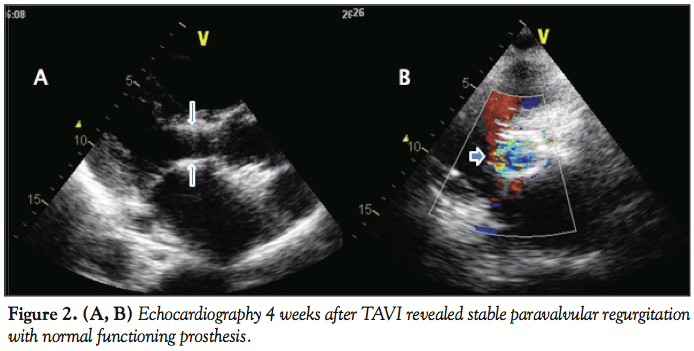

Echocardiography 4 weeks after TAVI revealed stable paravalvular regurgitation with normal functioning prosthesis (Figures 2A-2B). At approximately 80 days postimplantation, the patient was admitted for sepsis and Staphylococcus epidermidis was isolated on 3 separate blood cultures. Inflammatory indexes of ESR and CRP were elevated. Transesophageal echocardiography revealed no clear evidence of vegetation on the bioprosthesis. The patient was treated empirically for probable early prosthetic valve endocarditis with intravenous antibiotics for 4 weeks. The blood cultures became serially negative and the indexes of inflammation returned to normal. At 12-month follow-up, the patient was doing well.